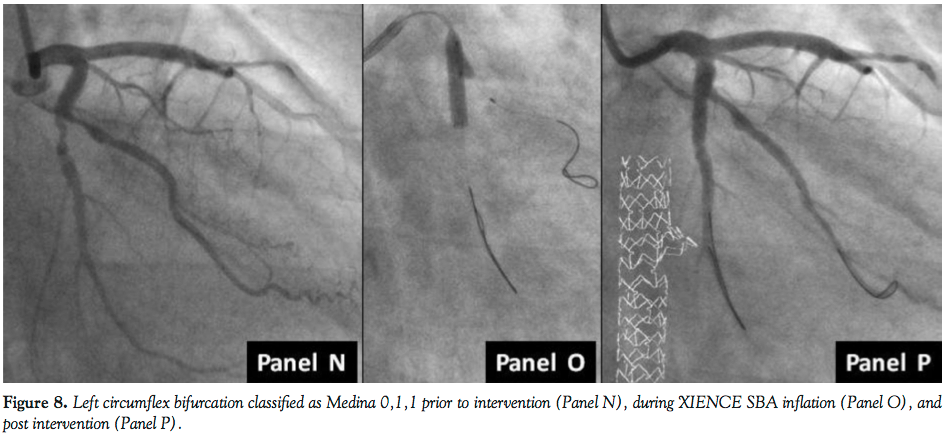

Figure 8 shows XIENCE SBA deployment as part of treating a Medina 0,1,1 lesion. Panel N represents the lesion prior to vessel balloon pretreatment. Following balloon angioplasty of the main branch, the device was inflated at pressures of 14 atm (Panel O) and the final result (Panel P) was achieved with no further postdeployment inflations.